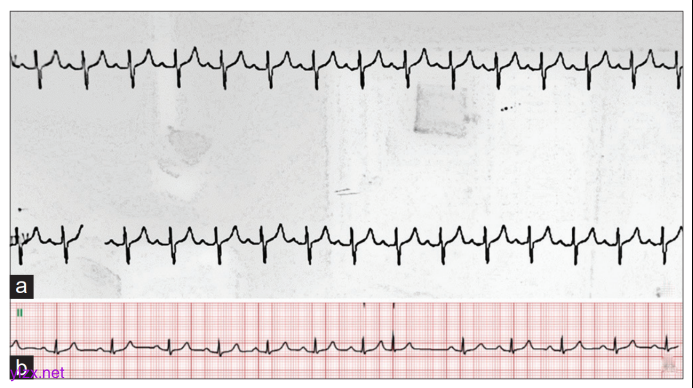

麻醉诱导及气管插管顺利,置入37Fr双腔气管导管(距门齿31cm),左侧卧位手术。单肺通气时间220分钟,潮气量约4.55mL/kg, ETCO2 31~40mmHg。术中II导联心电图示T波轻度抬高,与术前相似(图1)。术中静脉补液1500mL,尿量400mL,估计失血量约50mL。

图1 术中II导联心电图

(a)示 T 波轻度抬高,与术前心电图(b)表现一致